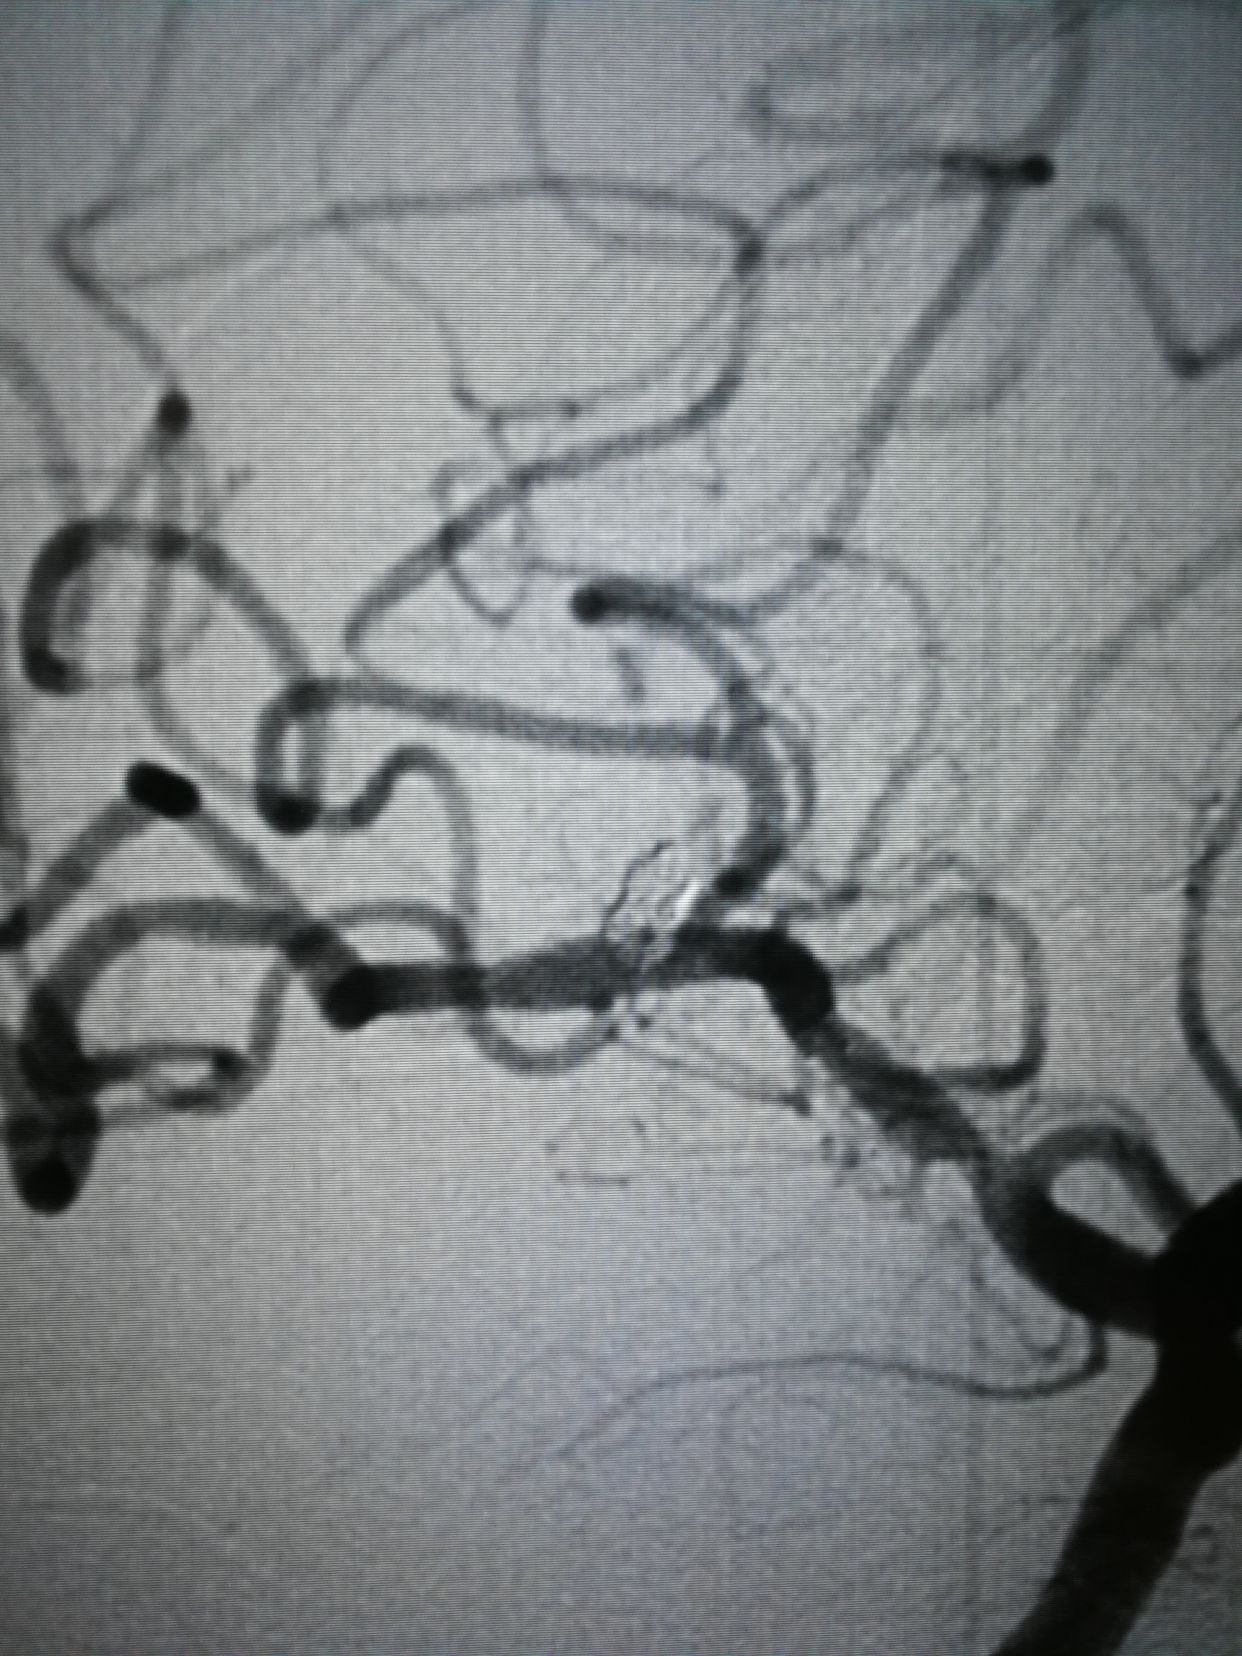

lvis25-17,支架打开很好,术后动脉瘤完全不显影。1个半小时结束战斗,收工回家。